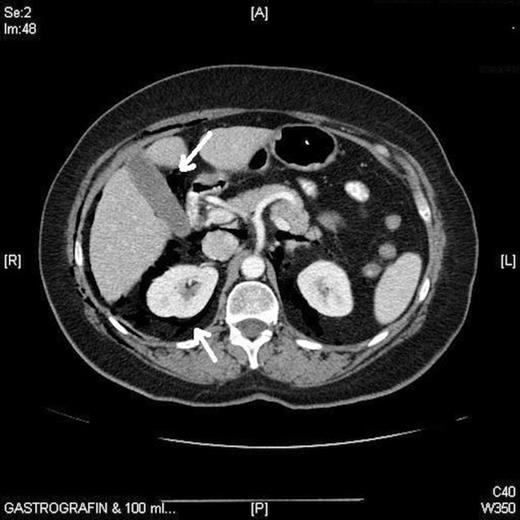

Full blood count was normal and a chest radiograph on admission showed subcutaneous emphysema, pneumo-mediastinum and pneumopericardium but no other abnormality (fig. 1). Computerised Tomography of the abdomen showed in addition, pneumoperitoneum and pneumoretroperitoneum (fig. 2). A water-soluble contrast examination of the colon failed to reveal evidence of a colonic perforation.

Immediate perforation is caused by direct trauma from excessive pressure or electrocautery; delayed perforation is usually due to necrosis. Brayko et al. investigated eleven sigmoid colons insufflated with air via colonoscope in human cadavers. Serosal tears occurred at mean pressure of 202 + 15mmHg, and mucosal rupture occurred at mean pressure of 226 + 14mmHg. They concluded that sigmoid perforations occurred more commonly as a result of instrument trauma rather than excessive insufflation (6). In our case minor subserosal tear was noticed after difficult hepatic flexure negotiation and the procedure was abandoned. Forcible herniation of the colonic mucosa becomes permeable to air without visible perforation and then the air may pass into the peritoneal cavity (complete perforation) or may lead to retroperitoneal gas collection and extension to the mediastinum and neck (incomplete perforation) (7). The reason is anatomical spread through the retroperitoneal fascial compartment, which extends through the posterior mediastinum to the neck. The air may enter the retroperitoneum via a mesenteric route, via direct perforation or even via pneumatosis cystoides coli; then it may dissect along structures passing into the periphery including the great vessels and psoas muscle as in our case. Mansfield and colleagues histologically demonstrated the existence of potential communication between the mediastinum and the pericardium at the ostia of the pulmonary veins (8) and this may explain the pneumopericardium in our patient.